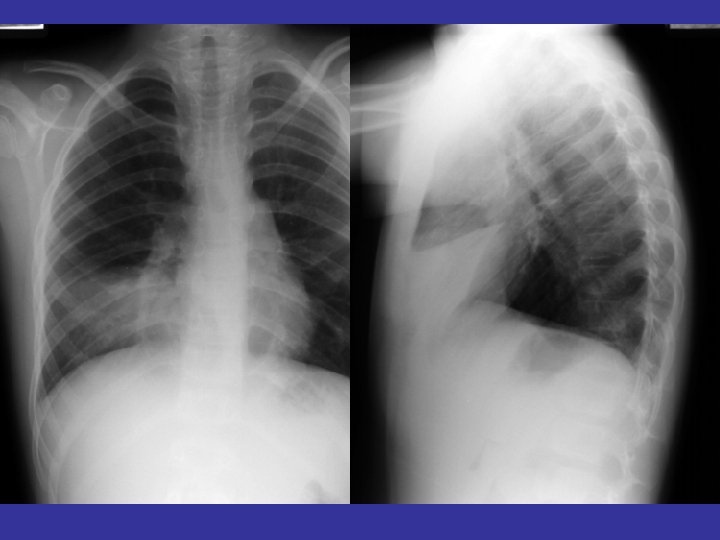

lateral view ? ! can detect otherwise hidden masses

The lateral chest film our best friend • Find abnormalities on the frontal film

The lateral chest film our best friend • Find abnormalities on the frontal film • Confirm abnormalities suspected from frontal film • Don’t be afraid to look at it